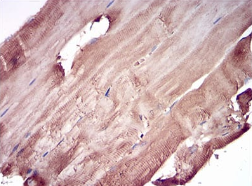

IHC    1/200 - 1/1000